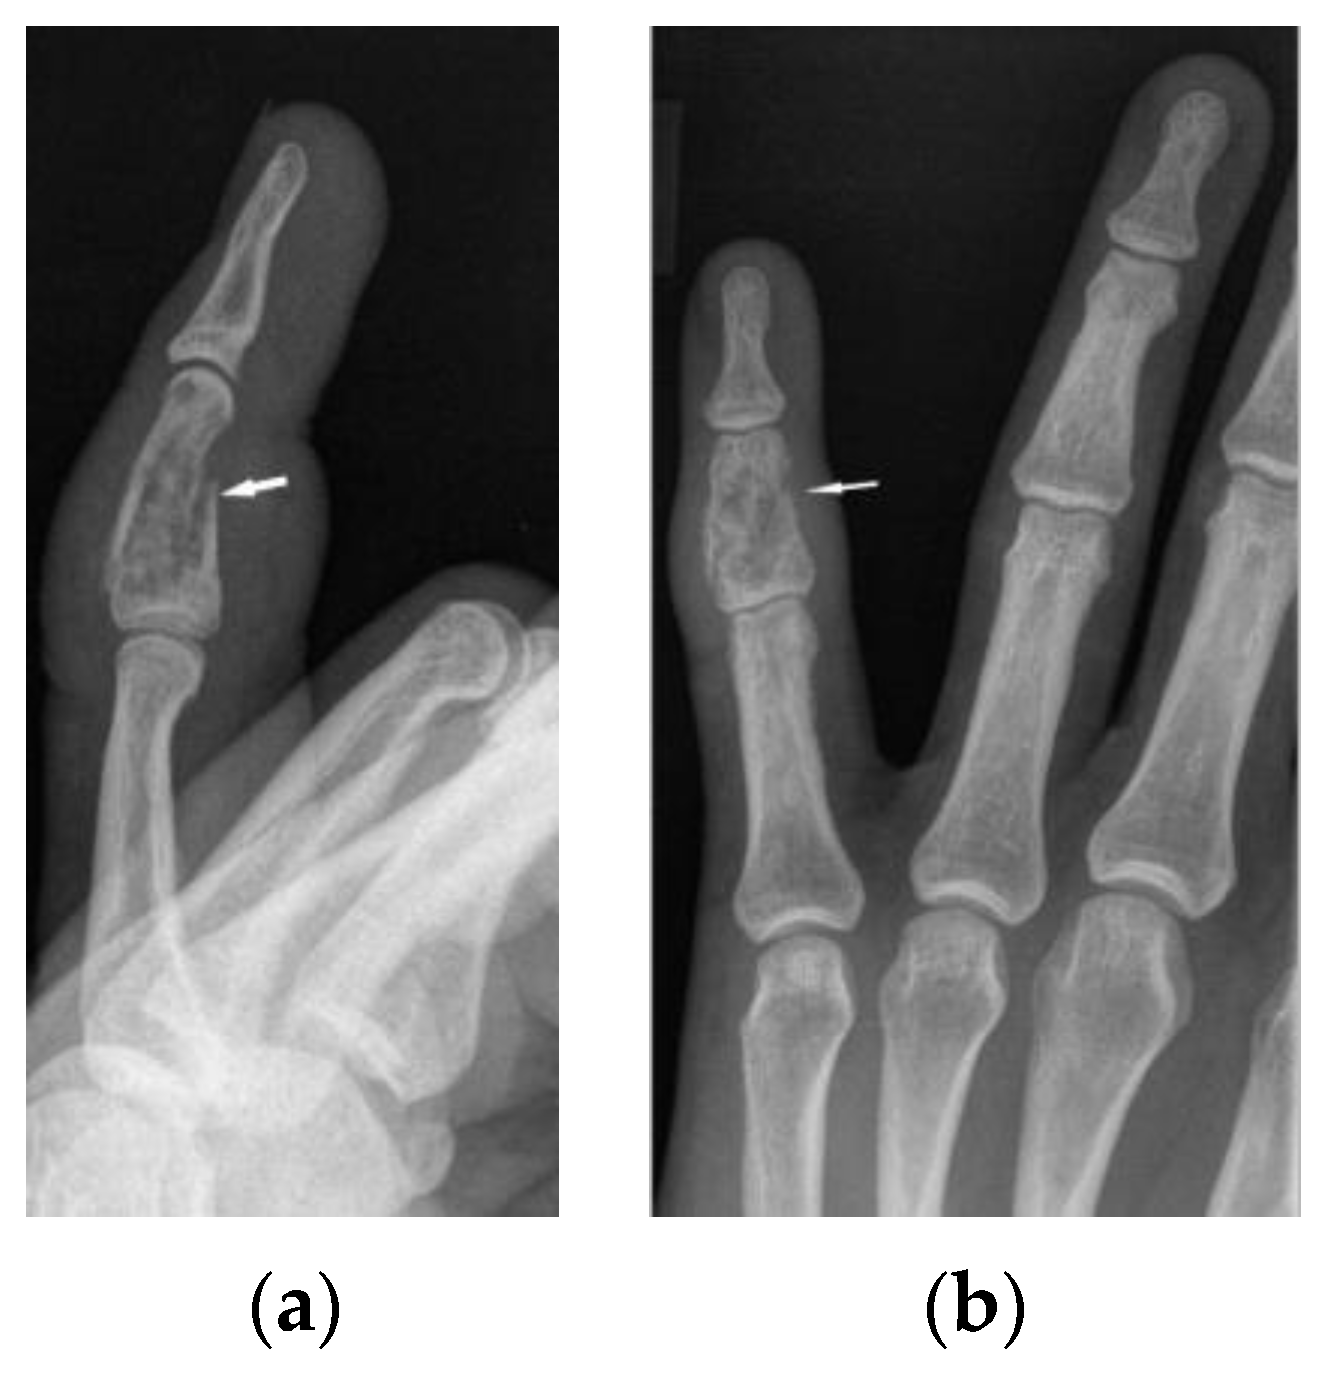

Figure 6. X-ray of the left hand, lateral view (a), PA (b). Osteolytic pattern in the middle phalanx with pathological fracture (white arrows). Soft tissue swelling.

The radiographic appearance of phalanges occupied by sarcoidosis includes lytic lesions of various sizes, called cysts. Cystic lesions, mostly punched-out, may be accompanied by soft tissue nodules. The presence of large cysts increase the risk of pathological bone fracture [20] (Figure 6a,b). Numerous small cysts are more frequently observed. The articular surfaces are preserved, although cysts located in the subchondral layer might mimic erosions (Figure 7). Periosteitis is uncommon.

Features of bony destruction may be permeative and cause scalloping of the cortex, whereby cortical margins are preserved. Bone destruction with moth-eaten pattern may involve the cortex, usually with associated soft tissue swelling [19]. The cortical and trabecular architecture is usually remodeled [20]. The phalanges of the second and third fingers of the hand are most often involved, leading to the image of sausage-shaped fingers [20].